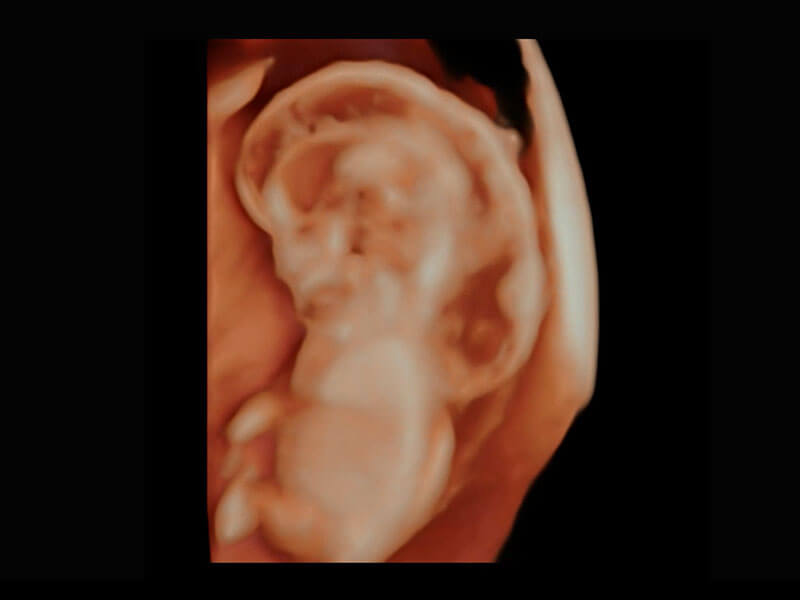

腔内三维-宫内节育器

腔内三维-光影成像

高分辨率容积成像-早孕胎儿